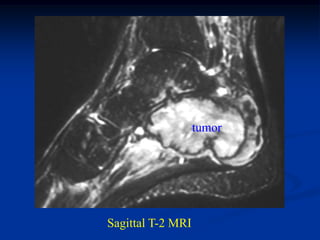

Case #1130            Metastatic Renal Cell

45 year male with metastatic renal cell CA to os calcis

Sagital T-1 MRI

tumor

Sagittal T-2 MRI

Axal T-1 MRI

Axial T-2 MRI

Photomic